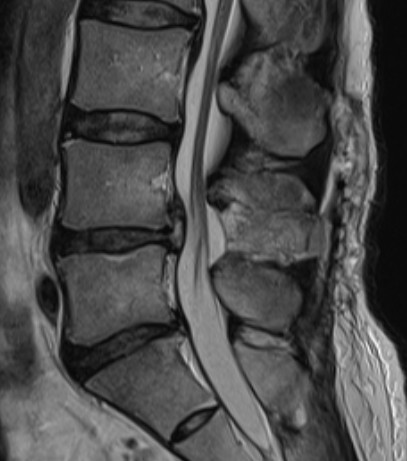

腰部脊柱管狭窄症

腰部脊柱管狭窄症は、背骨の中で腰骨(腰椎)の中を走行し、足に伸びていく神経が、腰骨の中(脊柱管)で圧迫される疾患です。これは加齢変化とともに起こります。症状は歩いていると足がしびれたり痛くなったり、重たくなったりします。

内服、リハビリ、ブロック注射でも改善しないときは手術を行っています。手術は神経の通り道を広げる手術(除圧術)を行います。さらに腰骨が不安定であったり、変性すべり症を伴っていたりするときは除圧術に腰骨を金属で固定する手術(固定術)を追加します。手術は可能な範囲で背筋を傷めない小侵襲手術を行っています。入院期間は約2週間、手術後はしばらくコルセットを装着して生活していただきます。当院で行っている脊椎手術で最も多い疾患です。